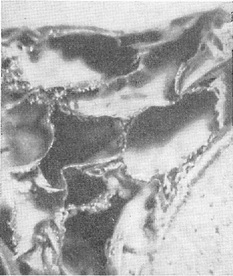

Ликвороносные канали - це мережа трубок, діаметр яких коливається від 3 мм до 200 мк (рис. 5). Найбільші канали повідомляються з цистернами основи мозку. Звідси канали поширюються по борознах великих півкуль і переходять на звивини. На своєму шляху канали рясно галузяться та анастомозують між собою. В ендотеліальних стінках каналів є отвори, за допомогою яких вони з'єднуються з ячеями. Канали - головні річища руху спинномозкової рідини. Цей рух має турбулентний характер і є вираженням двох по суті різних типів руху рідини: направленого від місця утворення до місця відтоку і коливального руху, обумовленого пульсацією судин, диханням і скороченням мускулатури.

![]() Рис. 5. Ликвороносный канал з розташованої в його просвіті артерією - поперечний переріз (микростереофотография трахископического препарату). |